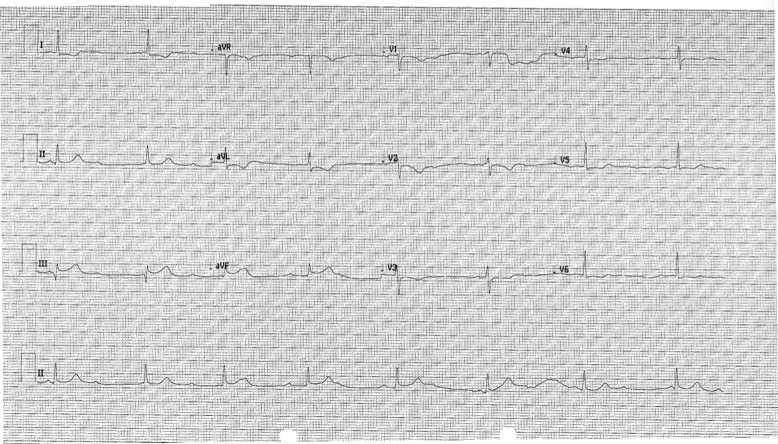

Case presentation: A 58-year-old female presented with New York Heart Association (NYHA) Class II symptoms resulting from severe, highly eccentric anterior mitral regurgitation from a bio-prosthetic valve. She had preserved ejection function and a total calcium score of zero. This patient underwent a re-do mechanical mitral valve replacement. Two days post-surgery, she was brought to the catheterization laboratory with signs and symptoms suggestive of an inferior myocardial infarction (MI) and complete heart block (CHB). Her symptoms and ST changes resolved immediately after the introduction of angiographic contrast. Angiography revealed no occlusion in the right coronary artery (RCA).